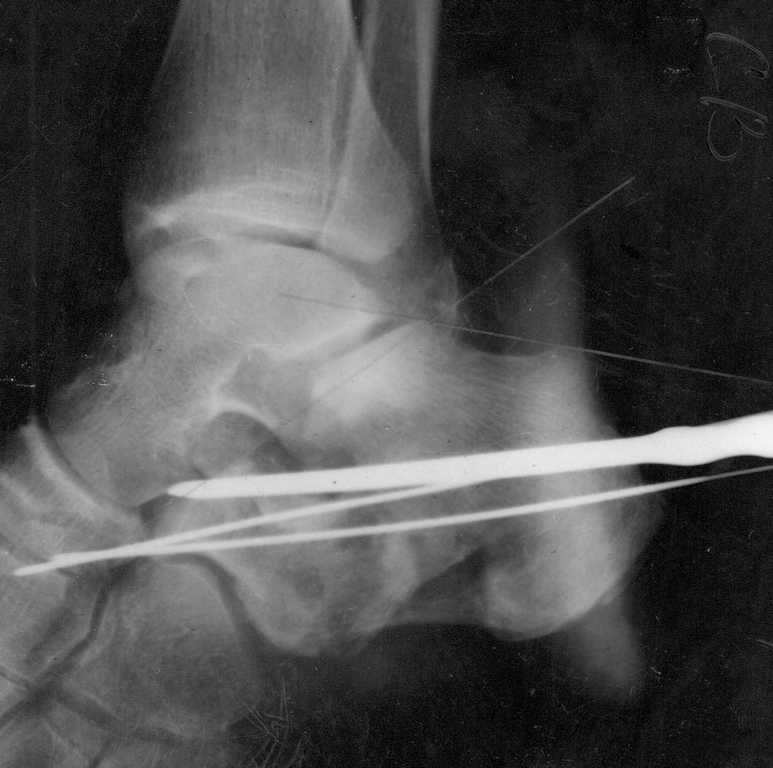

Re: Перелом пяточной кости

Сделали данному больному операцию. Фиксация перелома спицами. Это интраоперационный снимок.